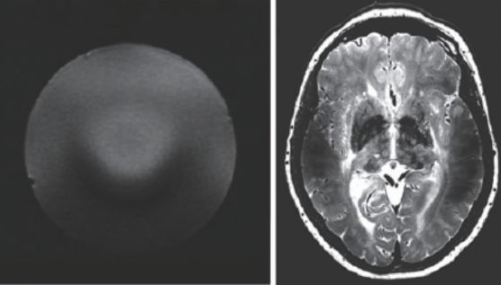

超高場(chǎng)MRI的射頻場(chǎng)設(shè)計(jì)也是一個(gè)較為困難的問(wèn)題。由于射頻頻率超過(guò)了300 MHz,介電常數(shù)引起的問(wèn)題非常突出。圖13 是一個(gè)在7 T 下的成像結(jié)果,可以看到在圖像內(nèi)部的信號(hào)非常不均勻,由于射頻波長(zhǎng)的極度縮短,組織的介電常數(shù)對(duì)射頻場(chǎng)的分布有極大的影響,這也是目前超高場(chǎng)MRI 需要解決的重要問(wèn)題之一。目前的9.4 T以上的MRI設(shè)備還難以獲得人體體部掃描的良好圖像,其主要應(yīng)用還是做頭部的掃描。

圖13 超高場(chǎng)下的射頻場(chǎng)不均勻性